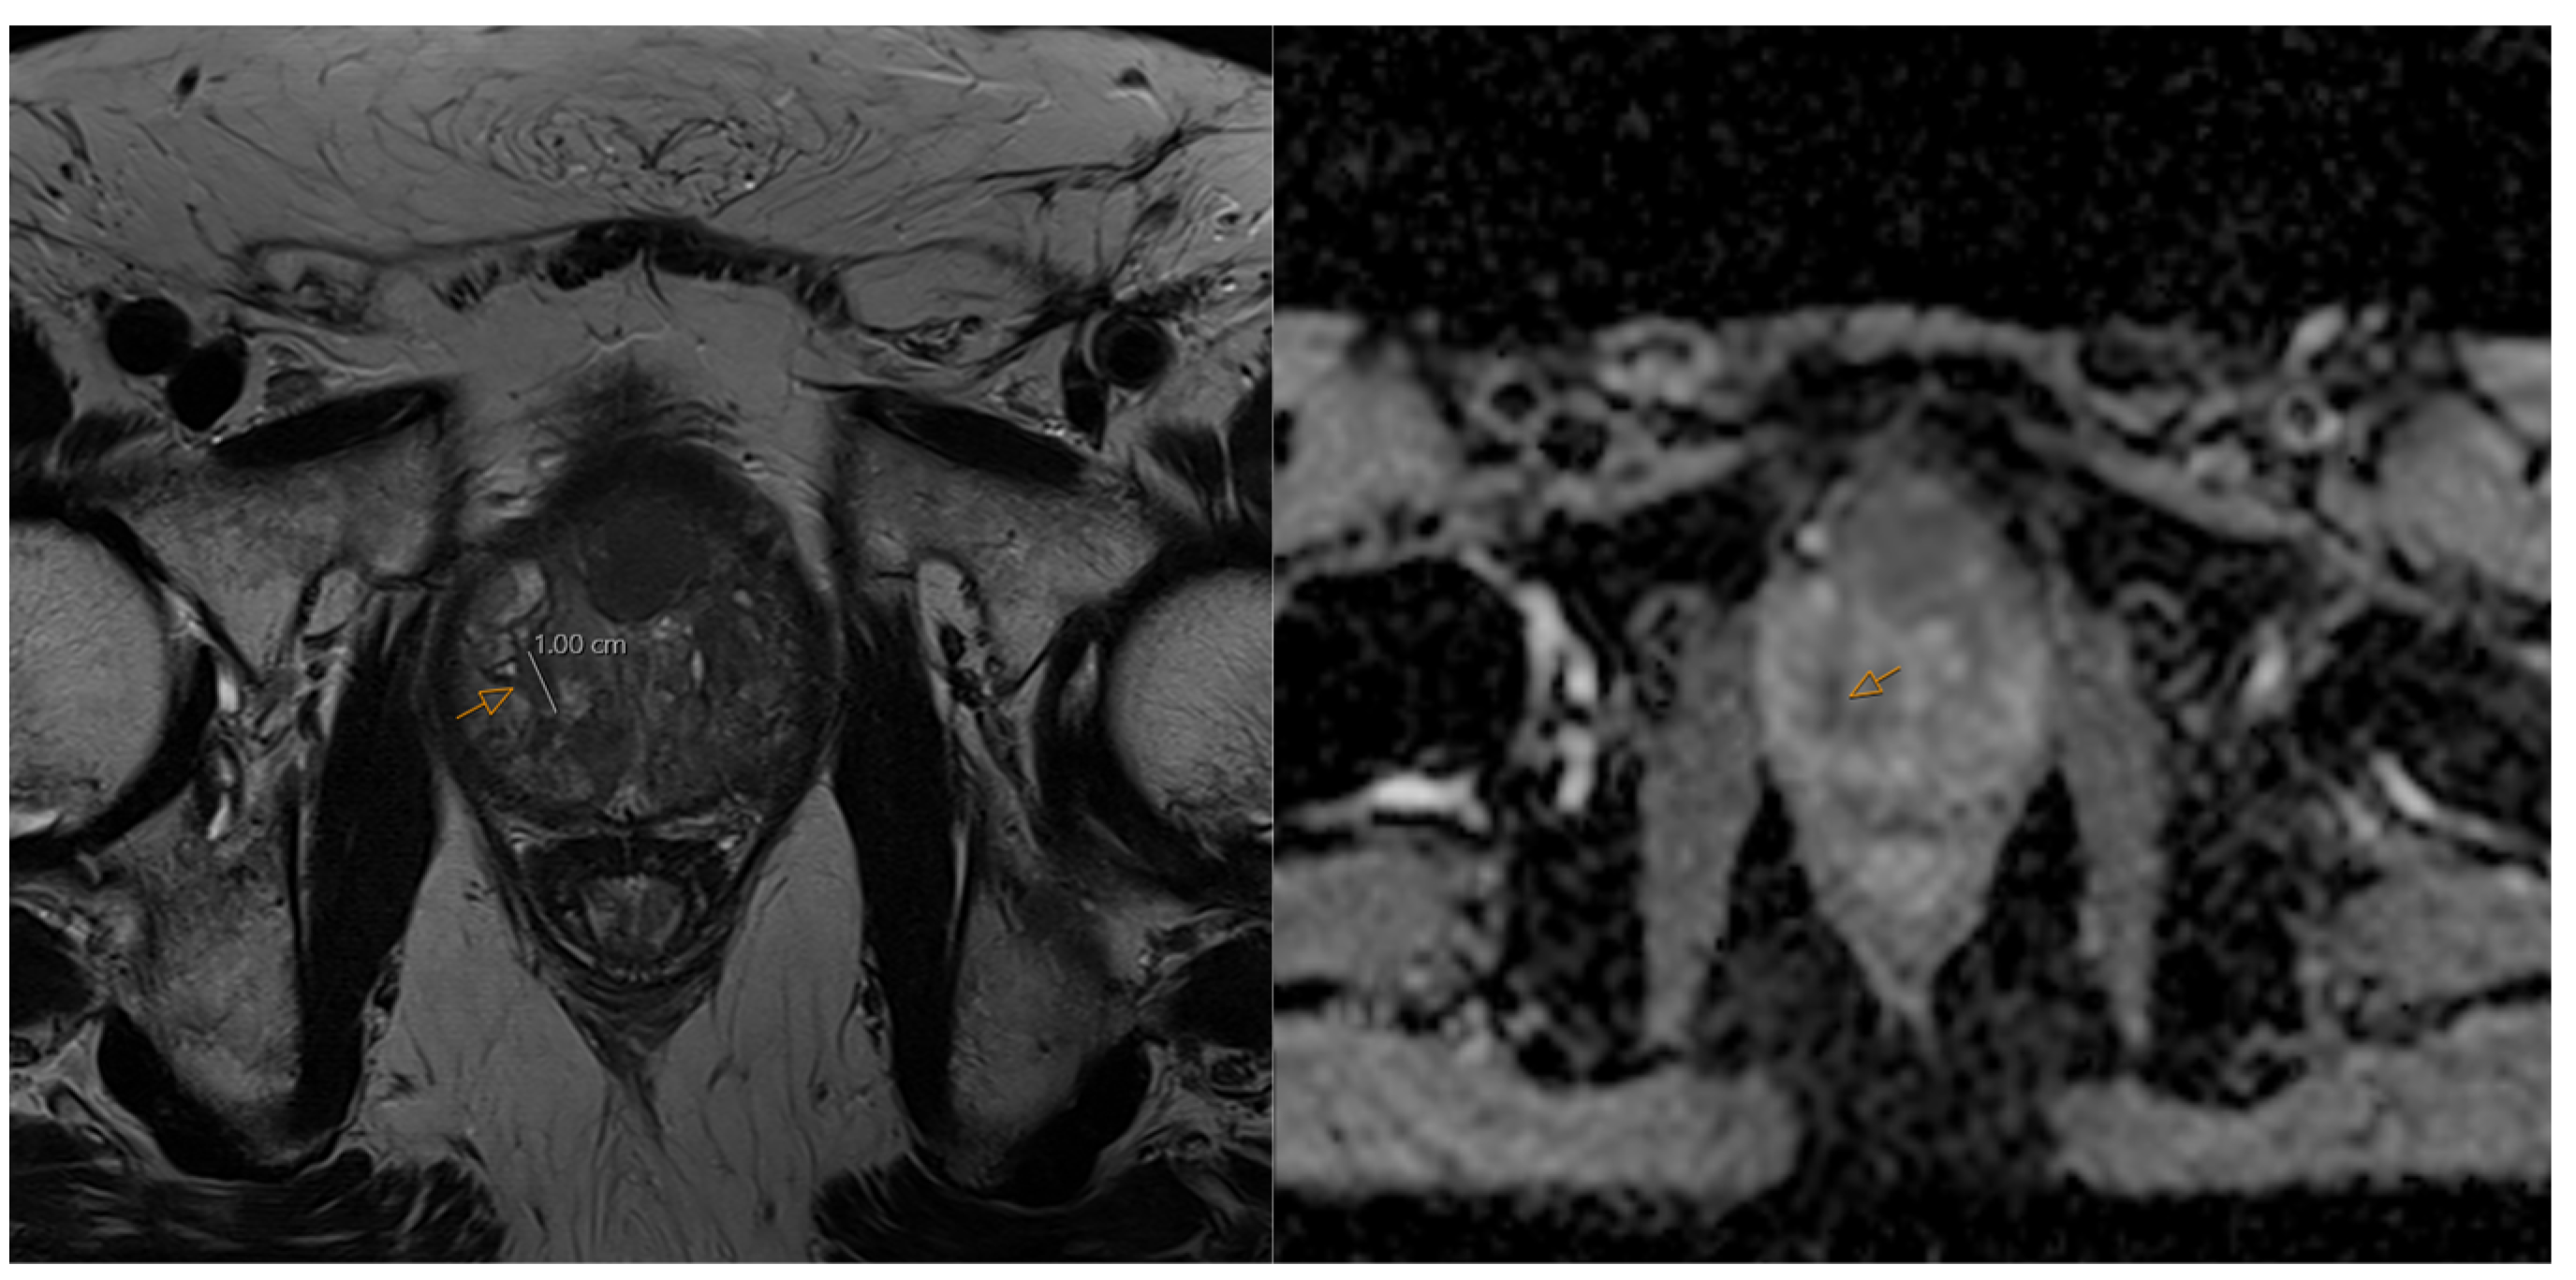

3. MRI, PSMA PET/CT, and Ultrasound in Prostate Cancer Imaging and Specific AI Applications